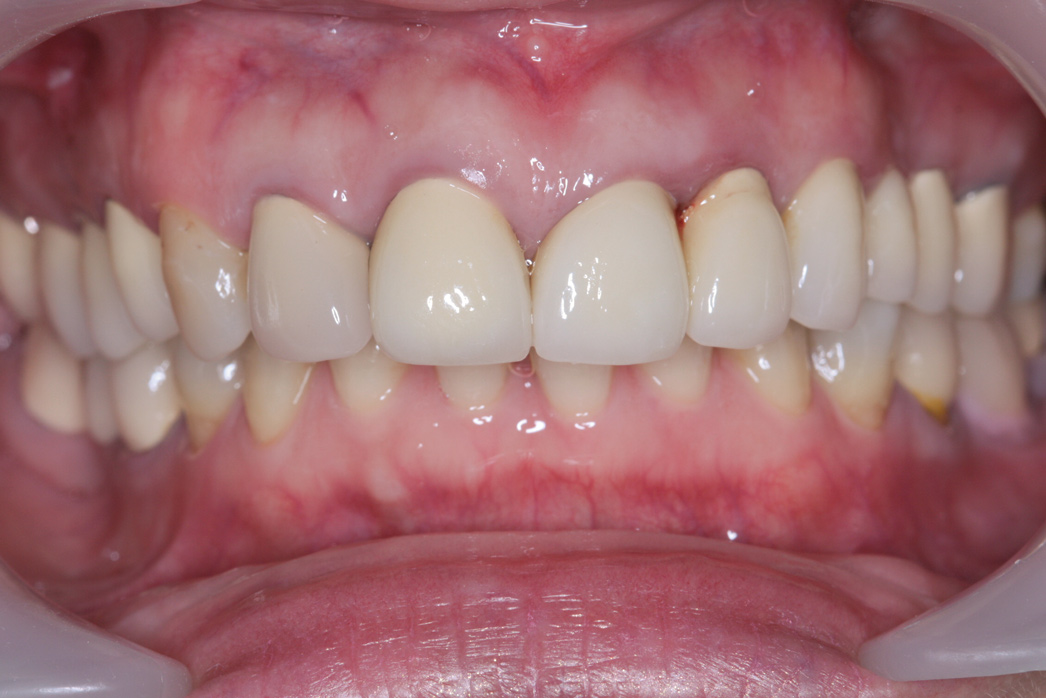

Post-treatment records showed a dramatic improvement in the patient's profile, smile, and dental esthetics and occlusion. The modified VDO had significantly increased the LAFH to achieve better facial proportion (UAFH/LAFH ratio of 50%/50%) and caused the depression of her chin to become shallower (Figure 9 and Figure 10). Intraorally, class I occlusion with well-aligned arch form and ideal overjet and overbite, esthetic upper anterior teeth size and proportion, good gingival margins, and proper prosthetic restorations were all achieved (Figure 11 and Figure 12).

Fig 11. Intraoral frontal view after treatment.

Figure 11